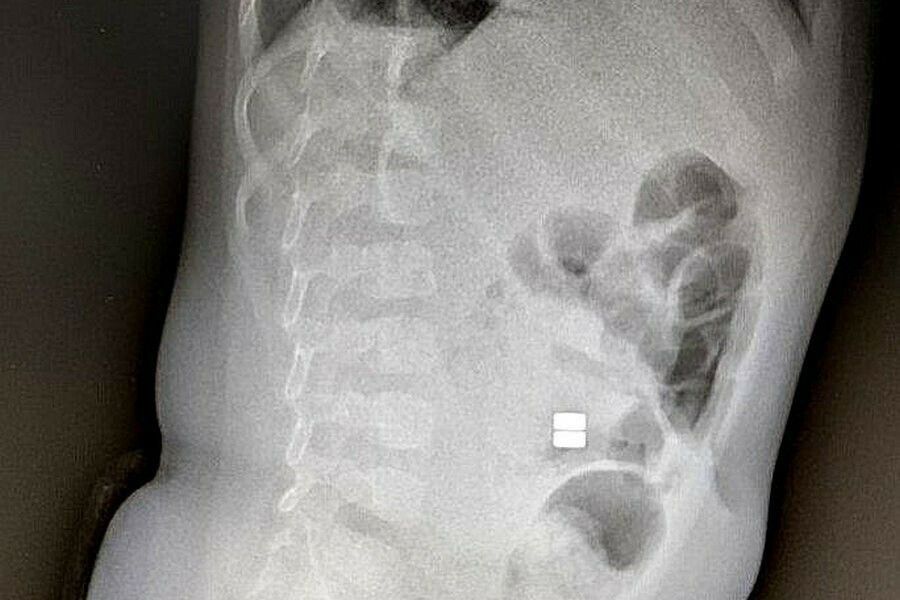

Ежедневно в Детскую областную больницу привозят детей с инородными телами.В Приамурье участились случаи обращений, связанных с проглатыванием детьми магнитных шариков. Подобные ситуации влекут за собой необратимые последствия для здоровья. Возраст...

Врачи бьют тревогу: маленькие амурчане все чаще попадают на операционный стол, проглотив магнитные шарикиАмурские медики бьют тревогу: дети все чаще глотают магнитные шарики. В группе риска — малыши от полугода до трех лет. Врачи...